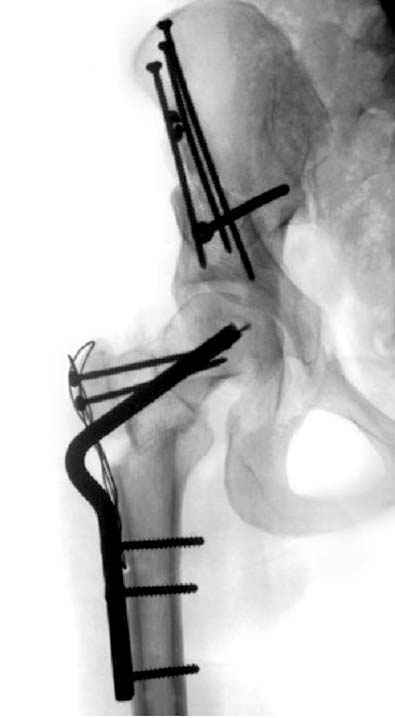

Но, занимаясь с этой патологией, собрал небольшой опыт в лечении остеоартрита, включая: периацетабулярную (ориентационно-корригирующую) остеотомию, и на проксимальной части бедра - valgus, varus, flexion and extension osteotomy и в комбинациях, базирующуюся на авангардных учениях Reinhold Ganz из Bern, на конгруентности сустава и увеличения контактной площади в суставе для уменьшения давления на площади хряща, При Вашем желании можно продемонстрировать результаты наших операций на слайдах.

Если Вам не трудно, не смогли бы Вы представить материал о том, в каких из перечисленных 1500 Ваших операций и 1500 ассистенциях, было применено Ваше открытие по коррекции тазобедренного сустава, потому что морфомеханика связана с варус или валгус остеотомиями на проксимальном отделе бедра.